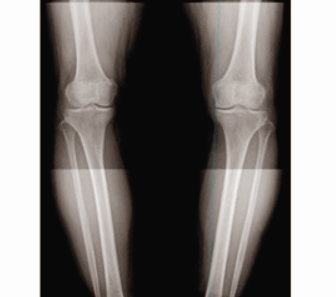

오다리 환자를 방사선촬영(X레이)을 해보면, 무릎의 안쪽 뼈가 거의 닿다시피 붙어있는 형태를 보인다.

이는 무릎의 연골이 닳아서 뼈 사이가 좁아진 이유도 있지만, 다리가 오자로 휘면서 무릎의 바깥쪽(외측)에 비해 안쪽(내측)의 틈새(연골)가 상대적으로 좁아지면서 부하와 염증이 잘 유발된다.